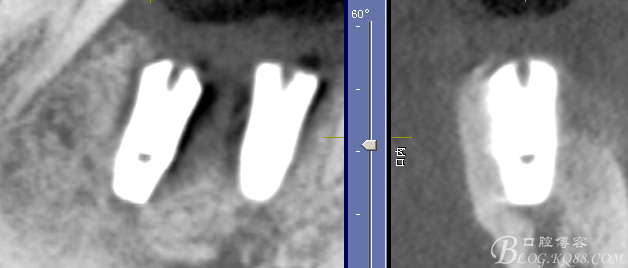

三維檢查種植體位置,方向,平行度

頰側軟組織凹陷明顯